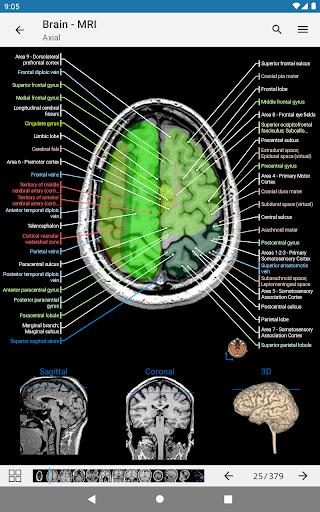

e-Anatomy tiene más de 26 000 imágenes que contienen series de imágenes en vistas axiales, coronales y sagitales, así como radiografías, angiografías, imágenes de disección, gráficos anatómicos e ilustraciones. Todas las imágenes médicas fueron etiquetadas cuidadosamente, más de 967 000 etiquetas disponibles en 12 idiomas, incluida la Terminologia Anatomica latina.

- Desplácese por los conjuntos de imágenes arrastrando el dedo

- Acerque y aleje el zoom

- Toque las etiquetas para mostrar las estructuras anatómicas

- Múltiples orientaciones de pantalla